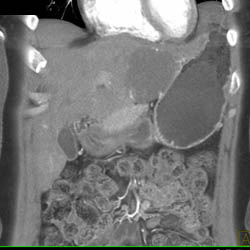

Hemangioma